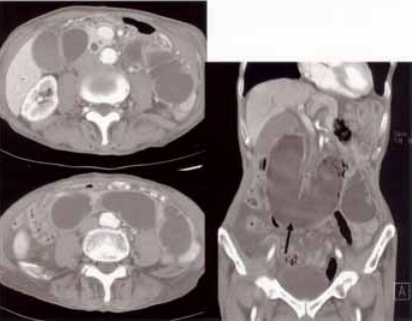

78 92 歲的張三老先生 在 10 年前因胃癌而接 , 受胃次全切除和胃空腸吻合手術。術後情 況良好。日前他又感到腹部脹痛而被家人 送醫。醫師診察發現腹部不正常,眼睛稍 黃,而為他做 CT 檢查。影像顯示小腸和膽 管不正常,如圖示。請問張三最有可能罹 患何症?

(A)無力性腸阻塞(adynamic ileus) (B)入端腸環症候群(afferent loop syndrome) (C)上腸繫膜動脈症候群(superior mesenteric artery syndrome) (D)環胰(annular pancreas)